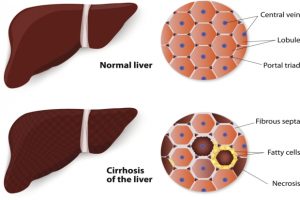

MRIs may soon replace invasive methods of testing fatty liver

In most diagnostic testing cases, in order to get the most accurate result, a biopsy much be taken and analyzed. This also tends to be the case with liver pathology, but according to a new study from Linköping University in Sweden, taking a tissue sample from the liver to diagnose fatty liver can be replaced ...click here to read more